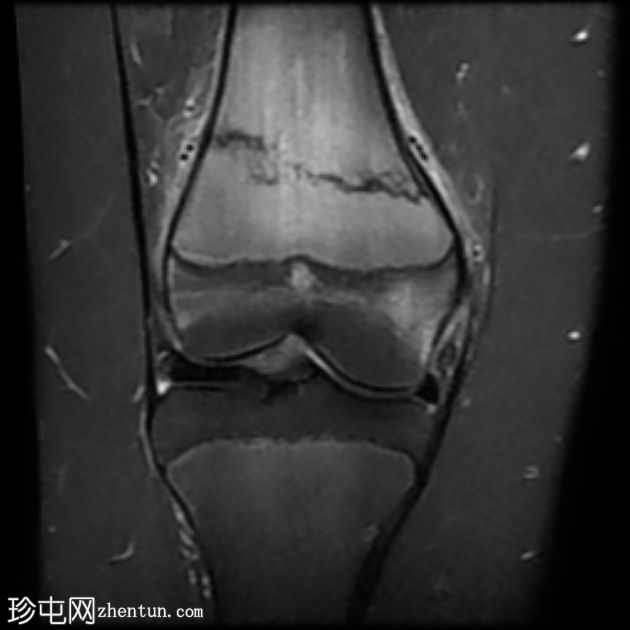

MRI

1.jpeg

冠状位

STIR

股骨远端干骺端横向应力骨折线,在所有脉冲序列(T1、T2和STIR)上均呈低信号。其周围有骨髓水肿样信号。邻近骨膜软组织呈水肿样信号。